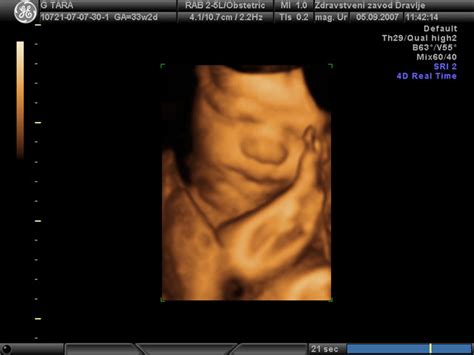

- Fetalni ultrazvok: Omogoča vizualizacijo ploda, oceno njegove rasti, anatomije in dobrobiti. V rizičnih nosečnostih se ultrazvoki izvajajo pogosteje.

- Spremljanje ploda: Nosečnosti z visokim tveganjem pogosto vključujejo natančno spremljanje otrokovega počutja, vključno s pogostimi ultrazvoki in specializiranimi testi za oceno rasti, gibanja in srčnega utripa ploda.